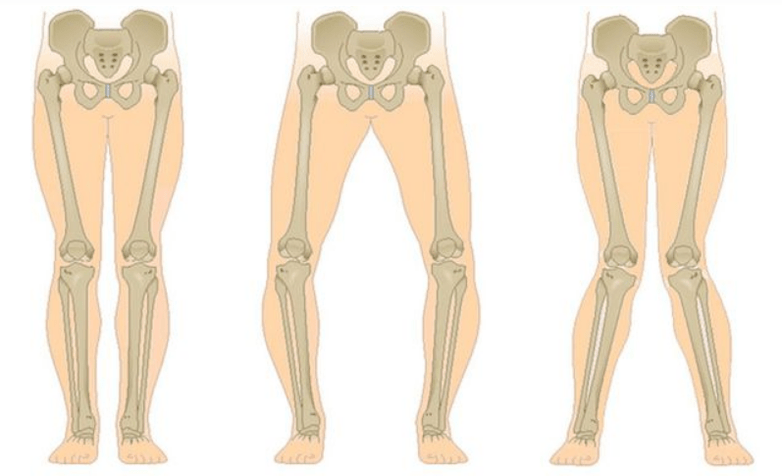

Kniedeformität

Die Konfiguration des Gelenks verändert sich, als würde es sich ausdehnen.

Das letzte Stadium der Gonarthrose ist dadurch gekennzeichnet, dass die Schmerzen nahezu konstant werden und nicht nur beim Gehen, sondern auch in Ruhe und sogar nachts, wenn die Patienten eine bequeme Schlafposition finden müssen, Angst verursachen. Die Bewegung ist eingeschränkter: Es ist schwierig, das Bein vollständig zu beugen und zu strecken. Das Gelenk verformt sich und nimmt an Volumen zu. Häufig kommt es zu einer Valgus- (X-förmigen) oder Varus- (O-förmigen) Deformität der Beine. Der Gang wird instabil und schwankt. In schweren Fällen sind ein Stock oder Krücken erforderlich.

Die häufigste Komplikation der Stadien II und III ist die Tendovaginitis der Adduktormuskelgruppe des Oberschenkels. Dies äußert sich durch Schmerzen an der Gelenkinnenfläche, die sich bei Bewegung verstärken. Die Ursache sind Ungleichgewichte und Muskelverformungen. Bei einer längeren Einschränkung der Bewegungsfreiheit entsteht eine Kontraktur. Darüber hinaus kommt es häufig zu einer Synovialitis.

Gonarthrose betrifft den gesamten Bewegungsapparat und verändert die Biomechanik der Wirbelsäule und anderer großer Gelenke der unteren Extremitäten. Dies kann zu Bandscheibenvorfällen und Arthritis anderer Gelenke führen. Das zweite Kniegelenk ist überlastet (bei einseitiger Erkrankung), da der Patient das schmerzende Bein verzeiht und das Gewicht auf das andere, gesunde Bein verlagert.